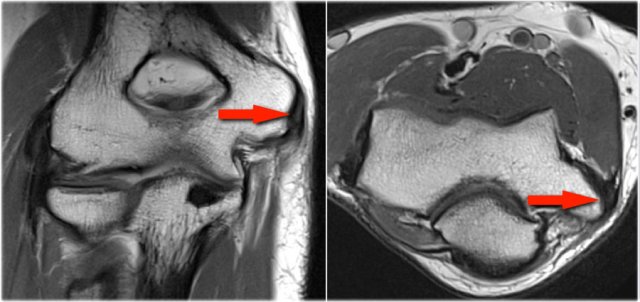

OC lesion of trochlea

These images are of a patient with anterior elbow pain.

There was no recent injury.

The clinical diagnosis was a biceps tendinitis or a bicipital bursitis.

The findings on the coronal MR-images are quite uncommon.

If you would see this in the capitellum you would call it an osteochondral lesion of the capitellum.

So this is called an osteochondral lesion of the trochlea.

Notice the small cystic changes (white arrow).

There is also a small cartilage defect.

An osteochondral lesion of the trochlea is usually seen in younger patients, who have an immature skeleton.

It is seen in the lateral trochlea like in this case due to repetitive hyperextension in an area with tenuous blood supply.

It is also seen in the medial trochlea due to laxity and posteromedial abutment.